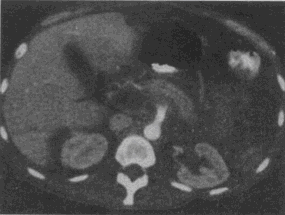

3.男,46歲,脾臟術后3天,右上腹痛,CT掃描如圖,最可能的診斷是

A.肝臟正常、脾臟術后改變

B.肝門脈血栓形成,脾臟術后改變

C.肝內膽管囊腫

D.膽總管下端結石

E.膽管細胞癌

正確答案:B解題思路:門脈管腔增大,管腔內可見軟組織影,未見強化,未見脾臟。